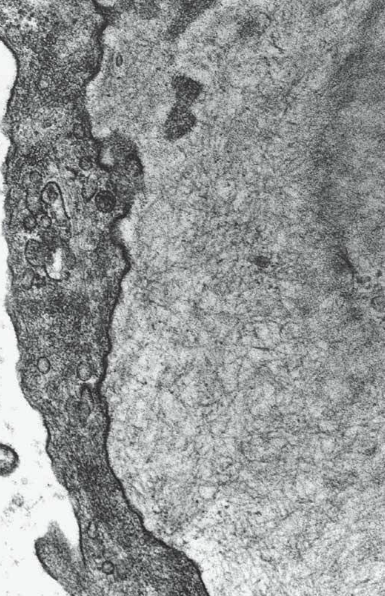

lamina densa of glomerular BM is laminated rather than forming a single dense band

hereditary nephritis aka Alport syndrome